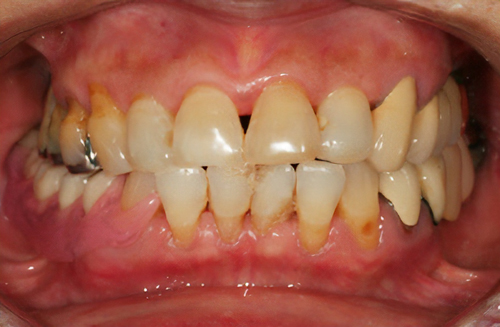

色調と透明感に優れる材料

金属を使用せず全てセラミックで作るので光を透過し、自然な色調、透明感を再現できます。

術前

術後

価格

> 55,000円~165,000円